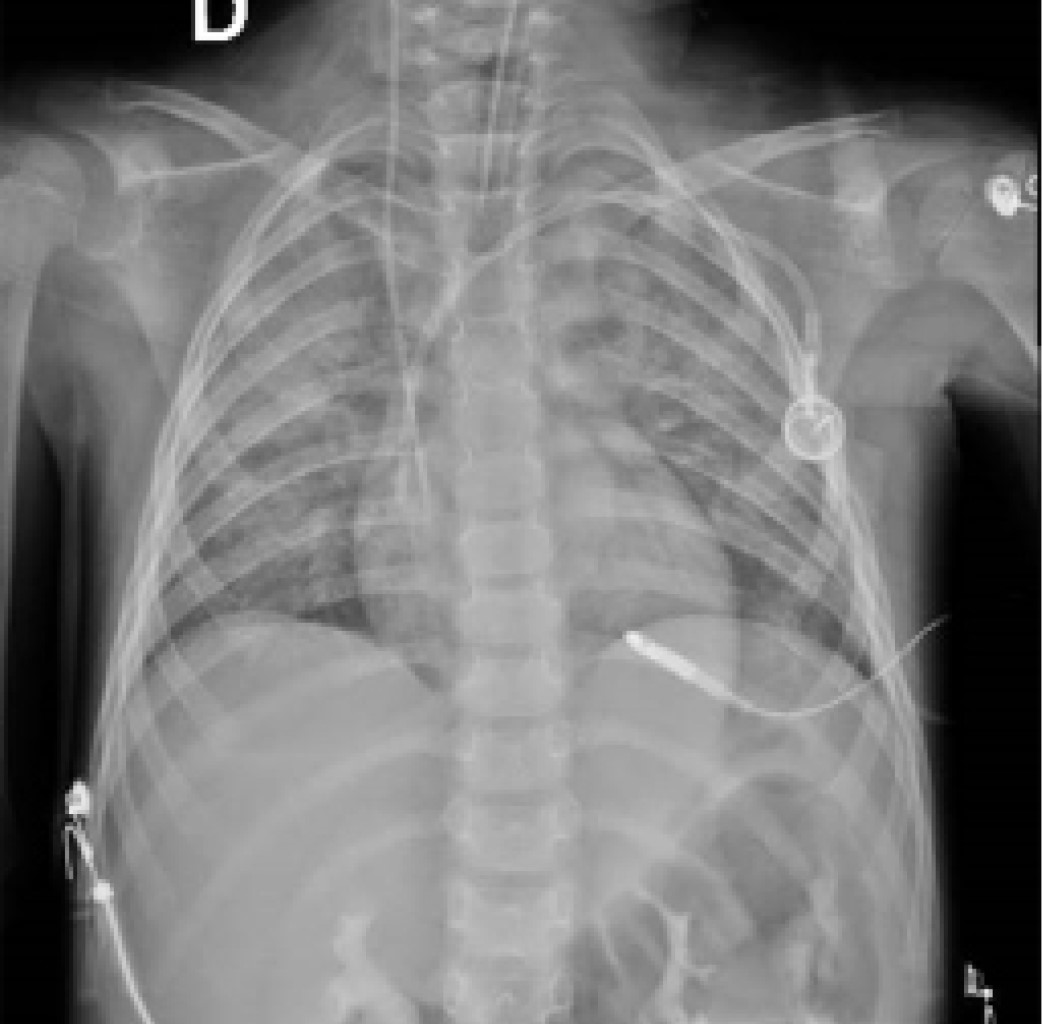

En la radiografía de tórax se muestra un patrón reti?culo-intersticial bilateral difuso, el cual inicia con opacidades centrales, con predominio en lóbulo medio o inferior (Figura 1).2,12-14 La tomografía computarizada de alta resolución es el método de elección radiológico y debe considerarse, incluso si las radiografías de tórax son normales. El hallazgo característico son las opacidades en vidrio despulido bilaterales (Figura 2).2,11,15

Figura 1